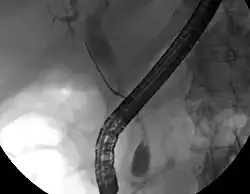

ERCP image of cholangiocarcinoma, showing common bile duct stricture and dilation of the proximal common bile duct

While abdominal imaging can be useful in the diagnosis of cholangiocarcinoma, direct imaging of the bile ducts is often necessary. Endoscopic retrograde cholangiopancreatography (ERCP), an endoscopic procedure performed by a gastroenterologist or specially trained surgeon, has been widely used for this purpose. Although ERCP is an invasive procedure with attendant risks, its advantages include the ability to obtain biopsies and to place stents or perform other interventions to relieve biliary obstruction.[12] Endoscopic ultrasound can also be performed at the time of ERCP and may increase the accuracy of the biopsy and yield information on lymph node invasion and operability.[56] As an alternative to ERCP, percutaneous transhepatic cholangiography (PTC) may be utilized. Magnetic resonance cholangiopancreatography (MRCP) is a non-invasive alternative to ERCP.[57][58][59] Some authors have suggested that MRCP should supplant ERCP in the diagnosis of biliary cancers, as it may more accurately define the tumor and avoids the risks of ERCP.[60][61][62]